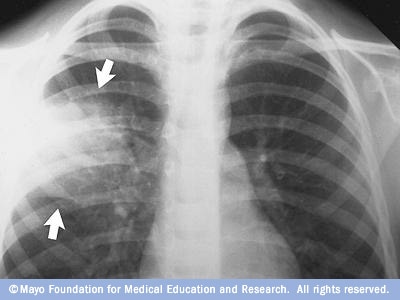

- Brust Röntgen. Röntgen hilft Ihrem Arzt, eine Lungenentzündung zu diagnostizieren und das Ausmaß und den Ort der Infektion zu bestimmen. Röntgen kann Ihrem Arzt jedoch nicht sagen, welche Art von Keim die Lungenentzündung verursacht.